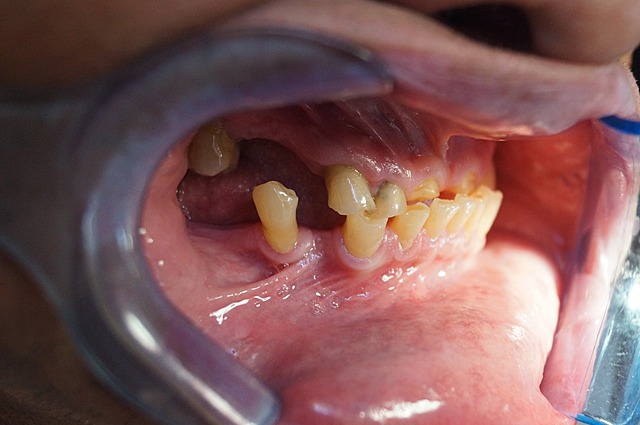

• Fotografías intraorales

Fotografías intraorales

Se observo Clase molar: no valorable clase canina: clase III

Bruxismo Severo, enfermedad periodontal con pérdida ósea horizontal.